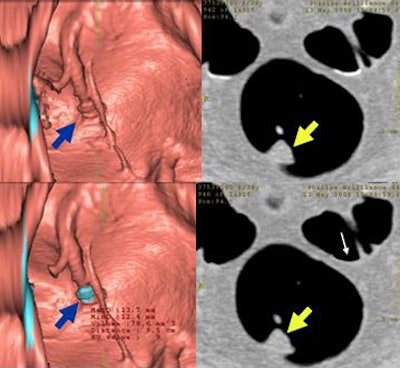

![]() |

| Without electronic cleansing, a 10-mm polyp was missed by CAD due to its flat morphology (top row above). After electronic cleansing was applied, CAD successfully detected this polyp (bottom row above). The lesion was confirmed as a well-differentiated adenocarcinoma on pathologic examination (below). |